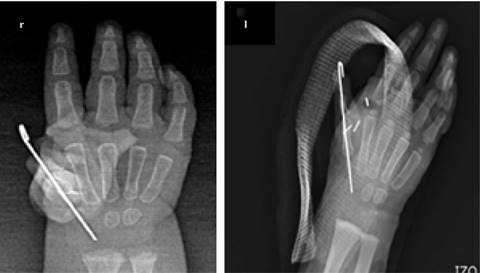

The closure of flaps was performed with 5-0 Nylon and, at the end of surgery, the thumb had a satisfactory aesthetic appearance, the attitude of the wrist in discrete flexion was still present, so we left a splint with a Spica, the only technical difference between surgeries was that a Hemoclip (vascular ligation) was used in the left hand (Figure 4). With ischemia on average of 97 min (99 min and 96 min respectively) and a total average surgical procedure duration of 193 min (197 min and 190 min respectively). We had no neurovascular complications.

Figure 4: Simple hand X-ray (postoperative): five fingers are observed in both hands, with a Kirschner in the first carpometacarpal joint in the form of a temporary fixation.